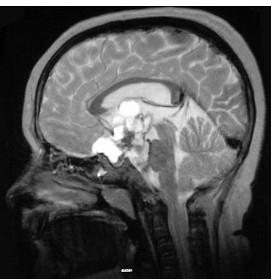

关于颅咽管瘤(见图)下列哪项不正确()A.男性多于女性B.囊性变且包膜钙化多见C.多见于成年人D.常发生在鞍上E.约占颅内肿瘤的5%

问题 关于颅咽管瘤(见图)下列哪项不正确()

选项 A.男性多于女性 B.囊性变且包膜钙化多见 C.多见于成年人 D.常发生在鞍上 E.约占颅内肿瘤的5%

答案 C